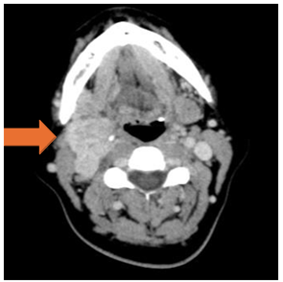

A computed tomography (CT) scan of the neck was performed, which showed the presence of an expansive, enhancing mass measuring 4.5 x 3 cm, centered in the carotid space, without a cleavage plane with the carotid artery or internal jugular vein. The mass had superior internal extension, partially occupying the parapharyngeal space and was inseparable from the right pharyngeal wall (figure 2).

Figure 2: Mass centered in the right carotid space (orange arrow).